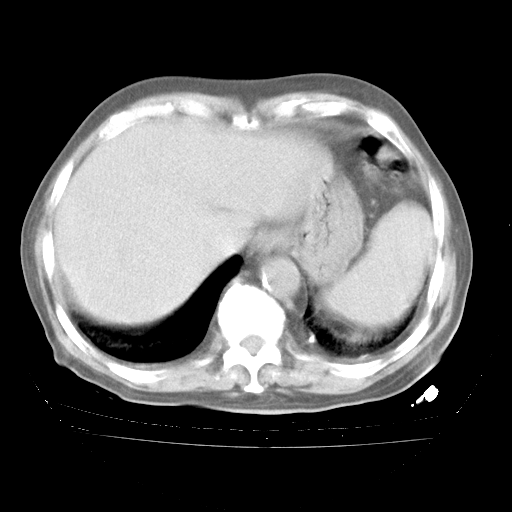

4月28日肺部CT